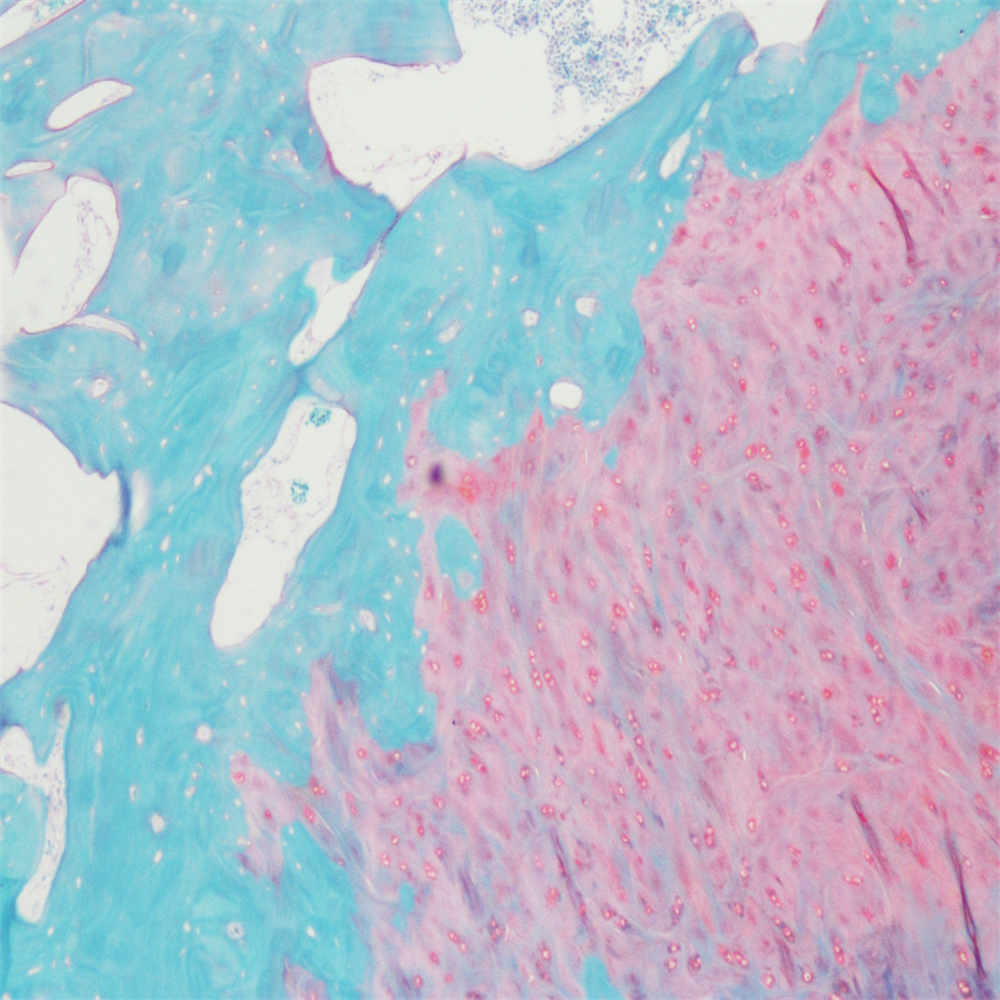

番红-固绿染色

番红-固绿染色(软骨)在涉及关节软骨及软骨下骨的形态学研究中,常需联合使用多种染料以显示其组织学结构。其中,起源于上世纪60年代的番红O(safranin O)-固绿(fast green)染色因可以直观反映关节软骨、软骨下骨和骨组织的结构而备受青睐。软骨呈红色,成骨呈绿色。

番红-固绿(软骨)染色法的染色原理在于嗜碱性的软骨和碱性染料番红O结合呈现红色,嗜酸性的骨和酸性染料固绿结合而成绿色或者蓝色,与呈现红色的软骨对比鲜明,从而将软骨组织和骨组织区分开。番红O是一种结合多阴离子的阳离子染料,其显示软骨组织是基于阳离子染料与多糖中阴离子基团(硫酸软骨素或硫酸角质素)结合。番红O着色与阴离子的浓度近似成正比关系,间接反映基质中蛋白多糖的含量和分布。当软骨收到损伤时,软骨中的糖蛋白会释放出来,使基质成分分布不均匀,从而导致番红O淡染或不着色。通过图像分析软件可以对番红O染色的软骨基质进行定量分析。固绿与胶原纤维结合,不宜褪色。